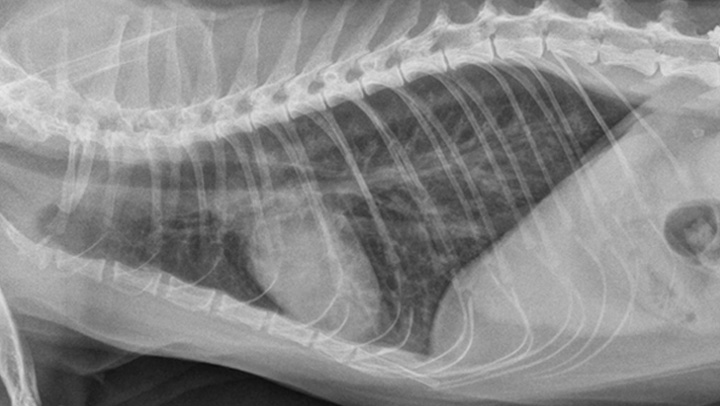

Primary cardiac disease that leads to CHF-related pulmonary edema commonly causes diffuse (perihilar in the dog) or variable (in the cat) interstitial and alveolar patterns. The vertebral heart score (VHS) is an objective method for evaluating the size of the cardiac silhouette (see Steps to Measure VHS). Certain cutoff values are used to determine whether acute respiratory distress is primarily pulmonary or cardiac in origin and to guide initial therapy for stabilization and planning for definitive cardiac or respiratory workup. A VHS <11.4 in the dog can help rule out mitral valve disease–related CHF as a cause for respiratory signs.3 Although an increased VHS can be associated with primary cardiac disease, it is not a specific characteristic in small-breed dogs because of their thoracic conformation.3 In the cat, a left lateral VHS ≤7.9 can reasonably rule out the presence of heart disease.4 Additional radiographic changes associated with primary cardiac disease include left atrial enlargement and pulmonary venous distension (Figures 1 and 2). Pleural effusion can be associated with CHF and primary pulmonary disease. A miliary pattern and/or solitary soft tissue densities in the lungs are indicative of primary pulmonary disease (Figure 3). Hyperinflation of the lung and distinct peribronchial markings are supportive of lower airway disease, although peribronchial markings can be found in the cat with CHF.

Mixed cardiac and pulmonary disease can exist in small animals with respiratory distress. For example, a dog may be presented with a history of mitral valve insufficiency but have clinical and radiographic evidence of aspiration pneumonia following a dental prophylaxis; or, a cat may present with a heart murmur and evidence of lower airway disease based on breathing pattern and thoracic radiographs (Figure 4; see image gallery above).